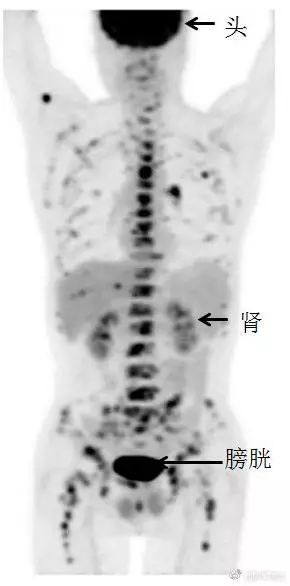

最后,再看一张震撼的全身PET/CT图像:除了黑色箭头所指的头、肾和膀胱外,全身其他部位的黑点都是肿瘤病变,全身90%以上骨头都有转移,而引起这么多转移的竟然是肺内一个1公分左右的小空洞病变。

全身PET/CT图上的除了头、肾、膀胱外,其余黑点基本上都是肿瘤病变